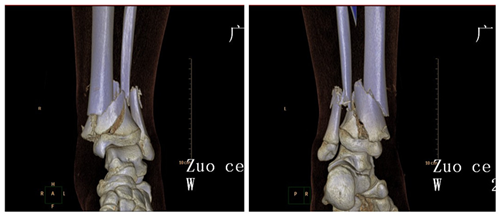

▲术前三维CT

术前根据患者左胫腓骨形态,使用远端CT三维重建数据打印出1:1比例的3D模型,再根据模型选择手术方案,包括切口的暴露,骨块的复位方法,以及塑形的固定钛板。